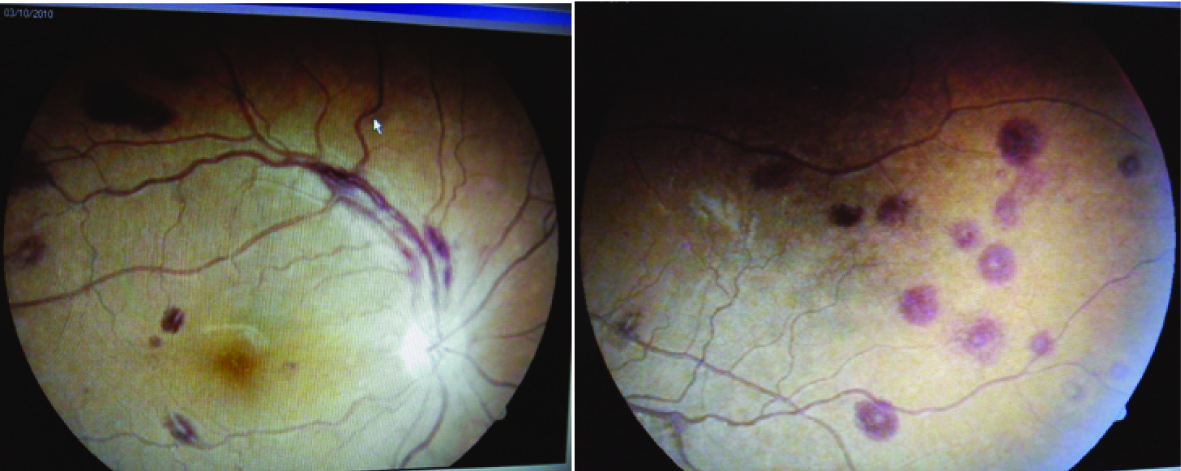

Two days after admission in the hospital he had history of sudden painless decrease in the vision from both eyes. His visual acuity in left eye was 6/9 and 9/12 in right eye. External ocular muscle movements were normal. Both pupils were round, equal, regular and reacting to direct and consensual light stimulus. Fundus examination revealed multiple retinal hemorrhages with white center and roth spots in all quadrants of fundus of both eyes. Retinal vessels were found tortuous. Papilledema, retinal whitening and exudates were absent [Table/Fig-1,2].

Retinal hemorrhages are frequently observed in Plasmodium falciparum infection, particularly with cerebral malaria in children but uncommon in non-cerebral malaria [2]. Malarial retinopathy includes various retinal changes and retinal signs in patients suffering from malaria. It includes retinal whitening, vessel changes, retinal hemorrhages and papilloedema. Retinal hemorrhages are very rare in Plasmodium vivax infestation [3–5]. The visual defects are usually reversible with complete recovery after treatment but rarely may be irreversible [6].

Malarial retinopathy is predominantly found in patients suffering from Plasmodium falciparum infestation with cerebral malaria in children but it can also be found in other form of malaria. Malarial retinopathy has also been found in adults with severe malaria and rare in Plasmodium vivax infestation [7]. It is characterized by retinal whitening (macular or perimacular), vessel changes (white or orange), retinal hemorrhage (particularly with white centres) and papilledema. Among these four changes, retinal whitening and vessel changes are specific and diagnostic of severe malarial disease [8]. The incidence of retinal haemorrhages was found in 46% cases of cerebral malaria [9]. This incidence was around 60% in children with cerebral malaria and was lower in less severe malarial disease [2].

Retinal hemorrhages in these patients usually absorbed spontaneously over the period of one to four weeks without retinal sequelae [9] and visual defect improved completely after successful treatment of malaria. Few cases have been reported with irreversible visual defects [7]. Our patient had peripheral parasitemia, severe anaemia, thrombocytopenia, hepatic dysfunction, mild renal dysfunction, raised CRP level and multiple retinal hemorrhages with white center. After successful treatment of malaria, he gained normal vision with normal visual acuity after one month. Thus we assume that severe vivax disease was responsible for retinal hemorrhages.